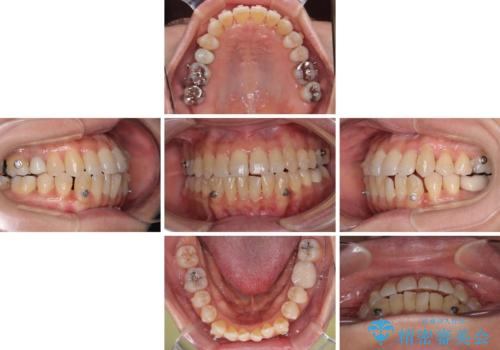

受け口と八重歯を改善 インビザライン矯正治療

受け口傾向の骨格であり、前歯はクロスバイトまたは切端咬合となっており、下顎を中心に歯列全体の後方移動を行い、IPR(歯と歯の間を削る)によってデコボコが解消するように設計し、インビザラインにより治療を行うこととしました。

受け口傾向のインビザライン矯正は比較的治療を行いやすいため、きれいに仕上げることができました。舌の突出癖が顕著であったため、改善のためのトレーニングをしっかりと行っていただきました。